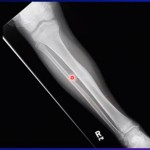

Osteoid Osteoma: Clinical Features and Management

Courtesy: Prof Nabil Ebraheim, University of Toledo, Ohio, USA